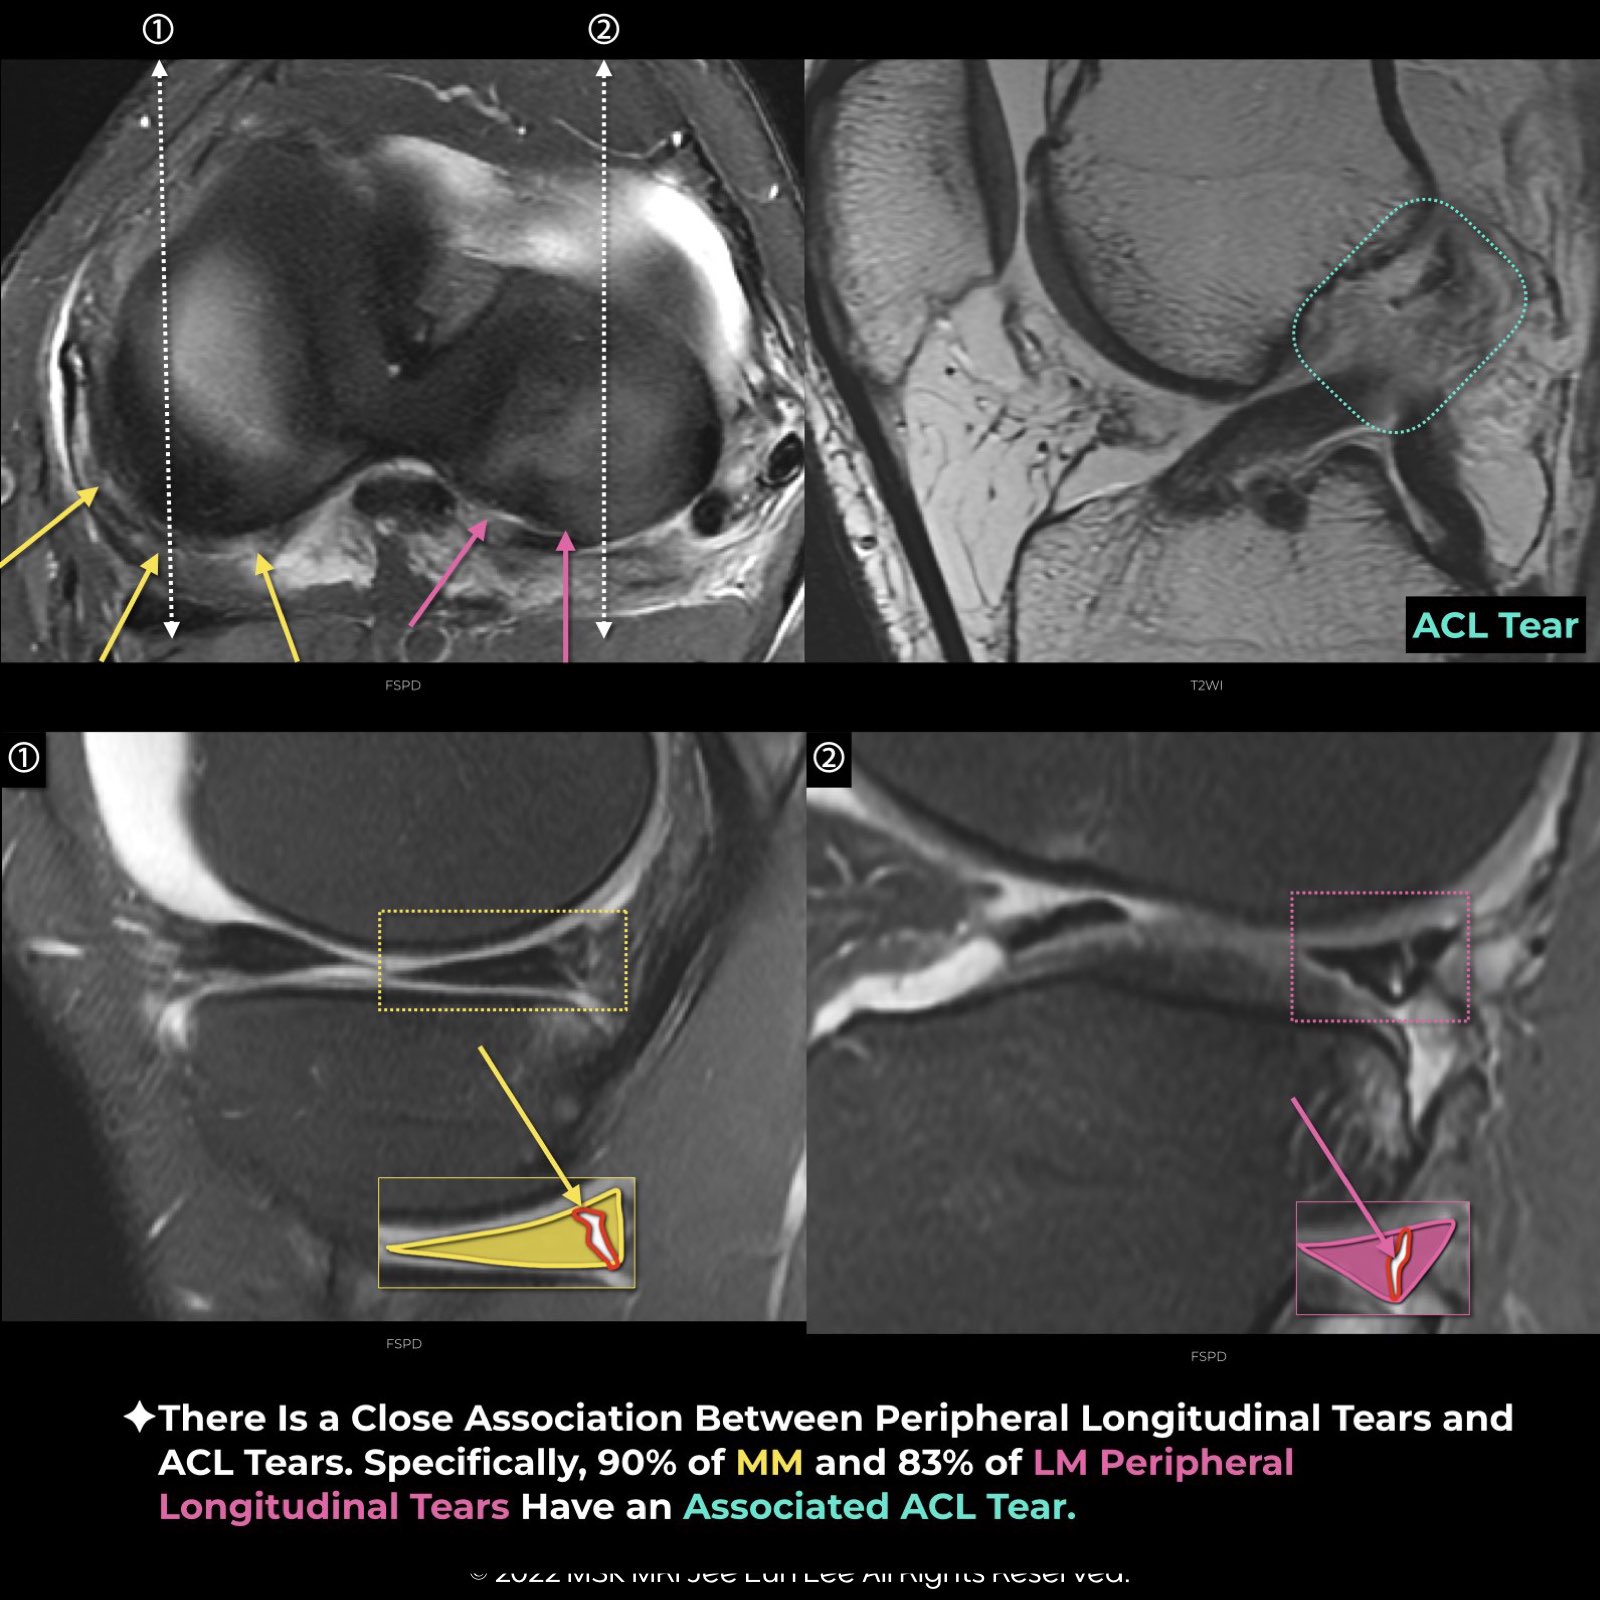

There is a strong link between peripheral longitudinal tears of the menisci and anterior cruciate ligament (ACL) tears. Specifically, about 90% of medial meniscus (MM) and 83% of lateral meniscus (LM) peripheral longitudinal tears are associated with ACL tears. Meniscal tears are found in 41-68% of acute isolated ACL injuries, 85-91% of chronic ACL-deficient knees, and up to 79% of pediatric cases. Meniscal repair, especially when combined with ACL reconstruction, has a better prognosis. Acute ACL injuries often involve lateral meniscal tears, whereas medial meniscal tears are more common in chronic ACL injuries.

The “Wrisberg Rip” is a specific type of longitudinal tear in the lateral meniscus. It starts at the junction of the posterior horn of the lateral meniscus and the meniscofemoral ligament, extending to the ligament’s attachment.

The “Type 4 Ramp lesion” of the medial meniscus is a full thickness vertical peripheral tear in the red-red zone of the medial meniscal posterior horn, identifiable by a high T2 fluid intensity signal from the superior to the inferior articular surface.